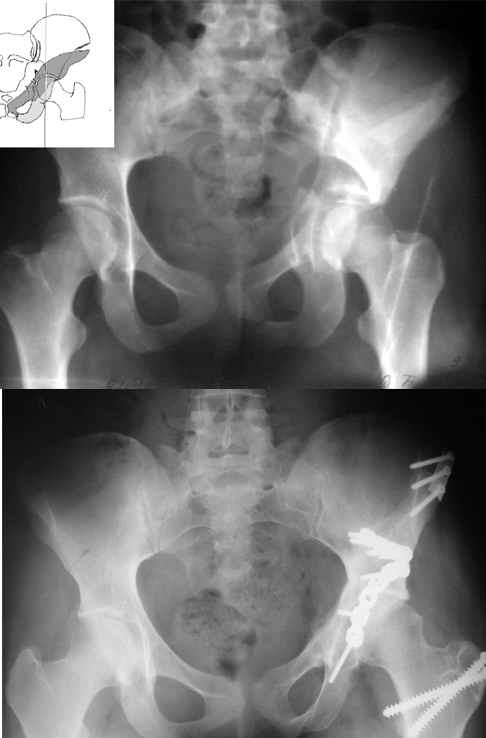

Уважаемые коллеги,43 летний мужчина, попав в автоаварию 13.10.2004, получил оскольчатый перелом обеих колонн левой вертлужной впадины.

На рентгенограммах - высокий двухколонный перелом вертлужной впадины с нарушением конгруэнтности, имеется обратная клиновидность суставной щели.

Спасибо за комментарии и рекомендации. Откровенно говоря, больного я прооперировал на прошлой неделе, через 5 дней после аварии и проблем с ним пока никаких нет, на удивление при достаточно обширной диссекции (илиофеморальный доступ) болей практически нет, так что больной самостоятельно садится в кровати, выполняет активные движения в оперированном суставе, сгибая до 60 градусов пока, далее с ассистенцией.

Причиной обращения к сообществу были возникшие непосредственно после операции сомнения и разочарования полученным качеством репозиции: а надо ли было трогать перелом вообще, репозиция передней колонны технически была очень сложна для меня, хотя реконструкции была в той же последовательности, что Д-р А.В.Рунков рекомендовал, в какой-то момент безуспешных манипуляций стал думать о *вторичной конгруэнтности*, которую не так давно обсуждали на

форуме и скелетном вытяжении. С репозицией и фиксацией задней колонны и отдельно задне-верхней стенки впадины проблем не возникло. Послеоп. Рг граммы в приложении. Если возникнут какие-либо дополнения или поправки - был бы признателен.

А какой отдел вертлужной впадины более важен передний или задний? Чем был обусловлен выбор доступа к суставу? Проще говоря, почему вы пошли передним доступом на двухколонный перелом? Мне понятны ваши сомнения, когда не удется сделать все что хотелось бы. В данном случае доступ должен быть чрезвертельным боковым (как и советовал Рунков) или двумя доступами.

Вопрос доступа к вертлужной впадине при остеосинтезе задача не простая. Конечно, у Летурнеля и Тайла всё давно описано, нам остается только брать на вооружение. Но сами понимаете, что не бывает двух одинаковых ситуаций, поэтому в каждом случае вопрос решается сугубо индивидуально. Наша главная цель - восстановить анатомию с нанесением минимальной дополнительной травмы тазобедреннному суставу, думаю с этим никто не поспорит. Расширенный илиофеморальный доступ уж слишком травматичен (как сказал один коллега "таз лежит отдельно, больной отдельно").Стоит ли делать из пациента анатомический препарат для того чтобы легче ориентироваться. Да и нужно ли собирать всю "мозаику"? Мы применяли при таких операциях своеобразную операционную хитрость - сначала устраняли грубое смещение крыла под гребнем с фиксацией так называемой "плавающей" пластиной (временно фиксированной на двух винтах)- доступ или продлевали боковой, или делали небольшой дополнительный разрез над гребнем. Это позволяло устранить грубое смещение и захождение отломков тела повздошной кости, что значительно облегчало репозицию и остеосинтез впадины над сводом. Основное внимание конечно же уделяли нагружаемому задне-верхнему отделу. Сообщите ваш адрес, пришлю схемы и рентгенограммы.